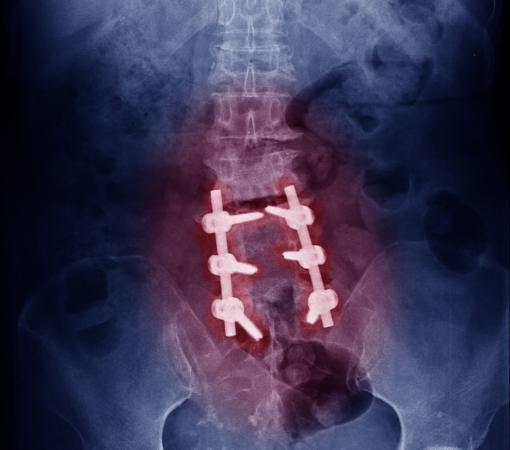

How Is Spinal Fusion Surgery in Mumbai Performed?

The affected vertebrae or discs are surgically removed.

A bone graft is placed to help the vertebrae fuse together.

Screws and metal rods may be inserted for stability.

Over time, the bones heal into a single solid structure.